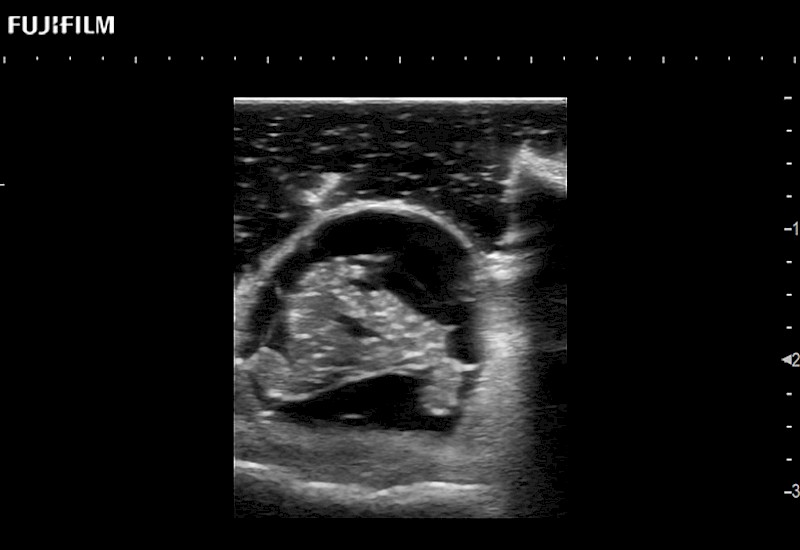

Exclusive 10mm side‐fire linear array transducer with 2.87mm diameter is ideal for real‐time visualization through and behind structures and instant, scalable definition of anatomy and vascularity including the ability to delineate and define tumor margins.

Main Specifications: